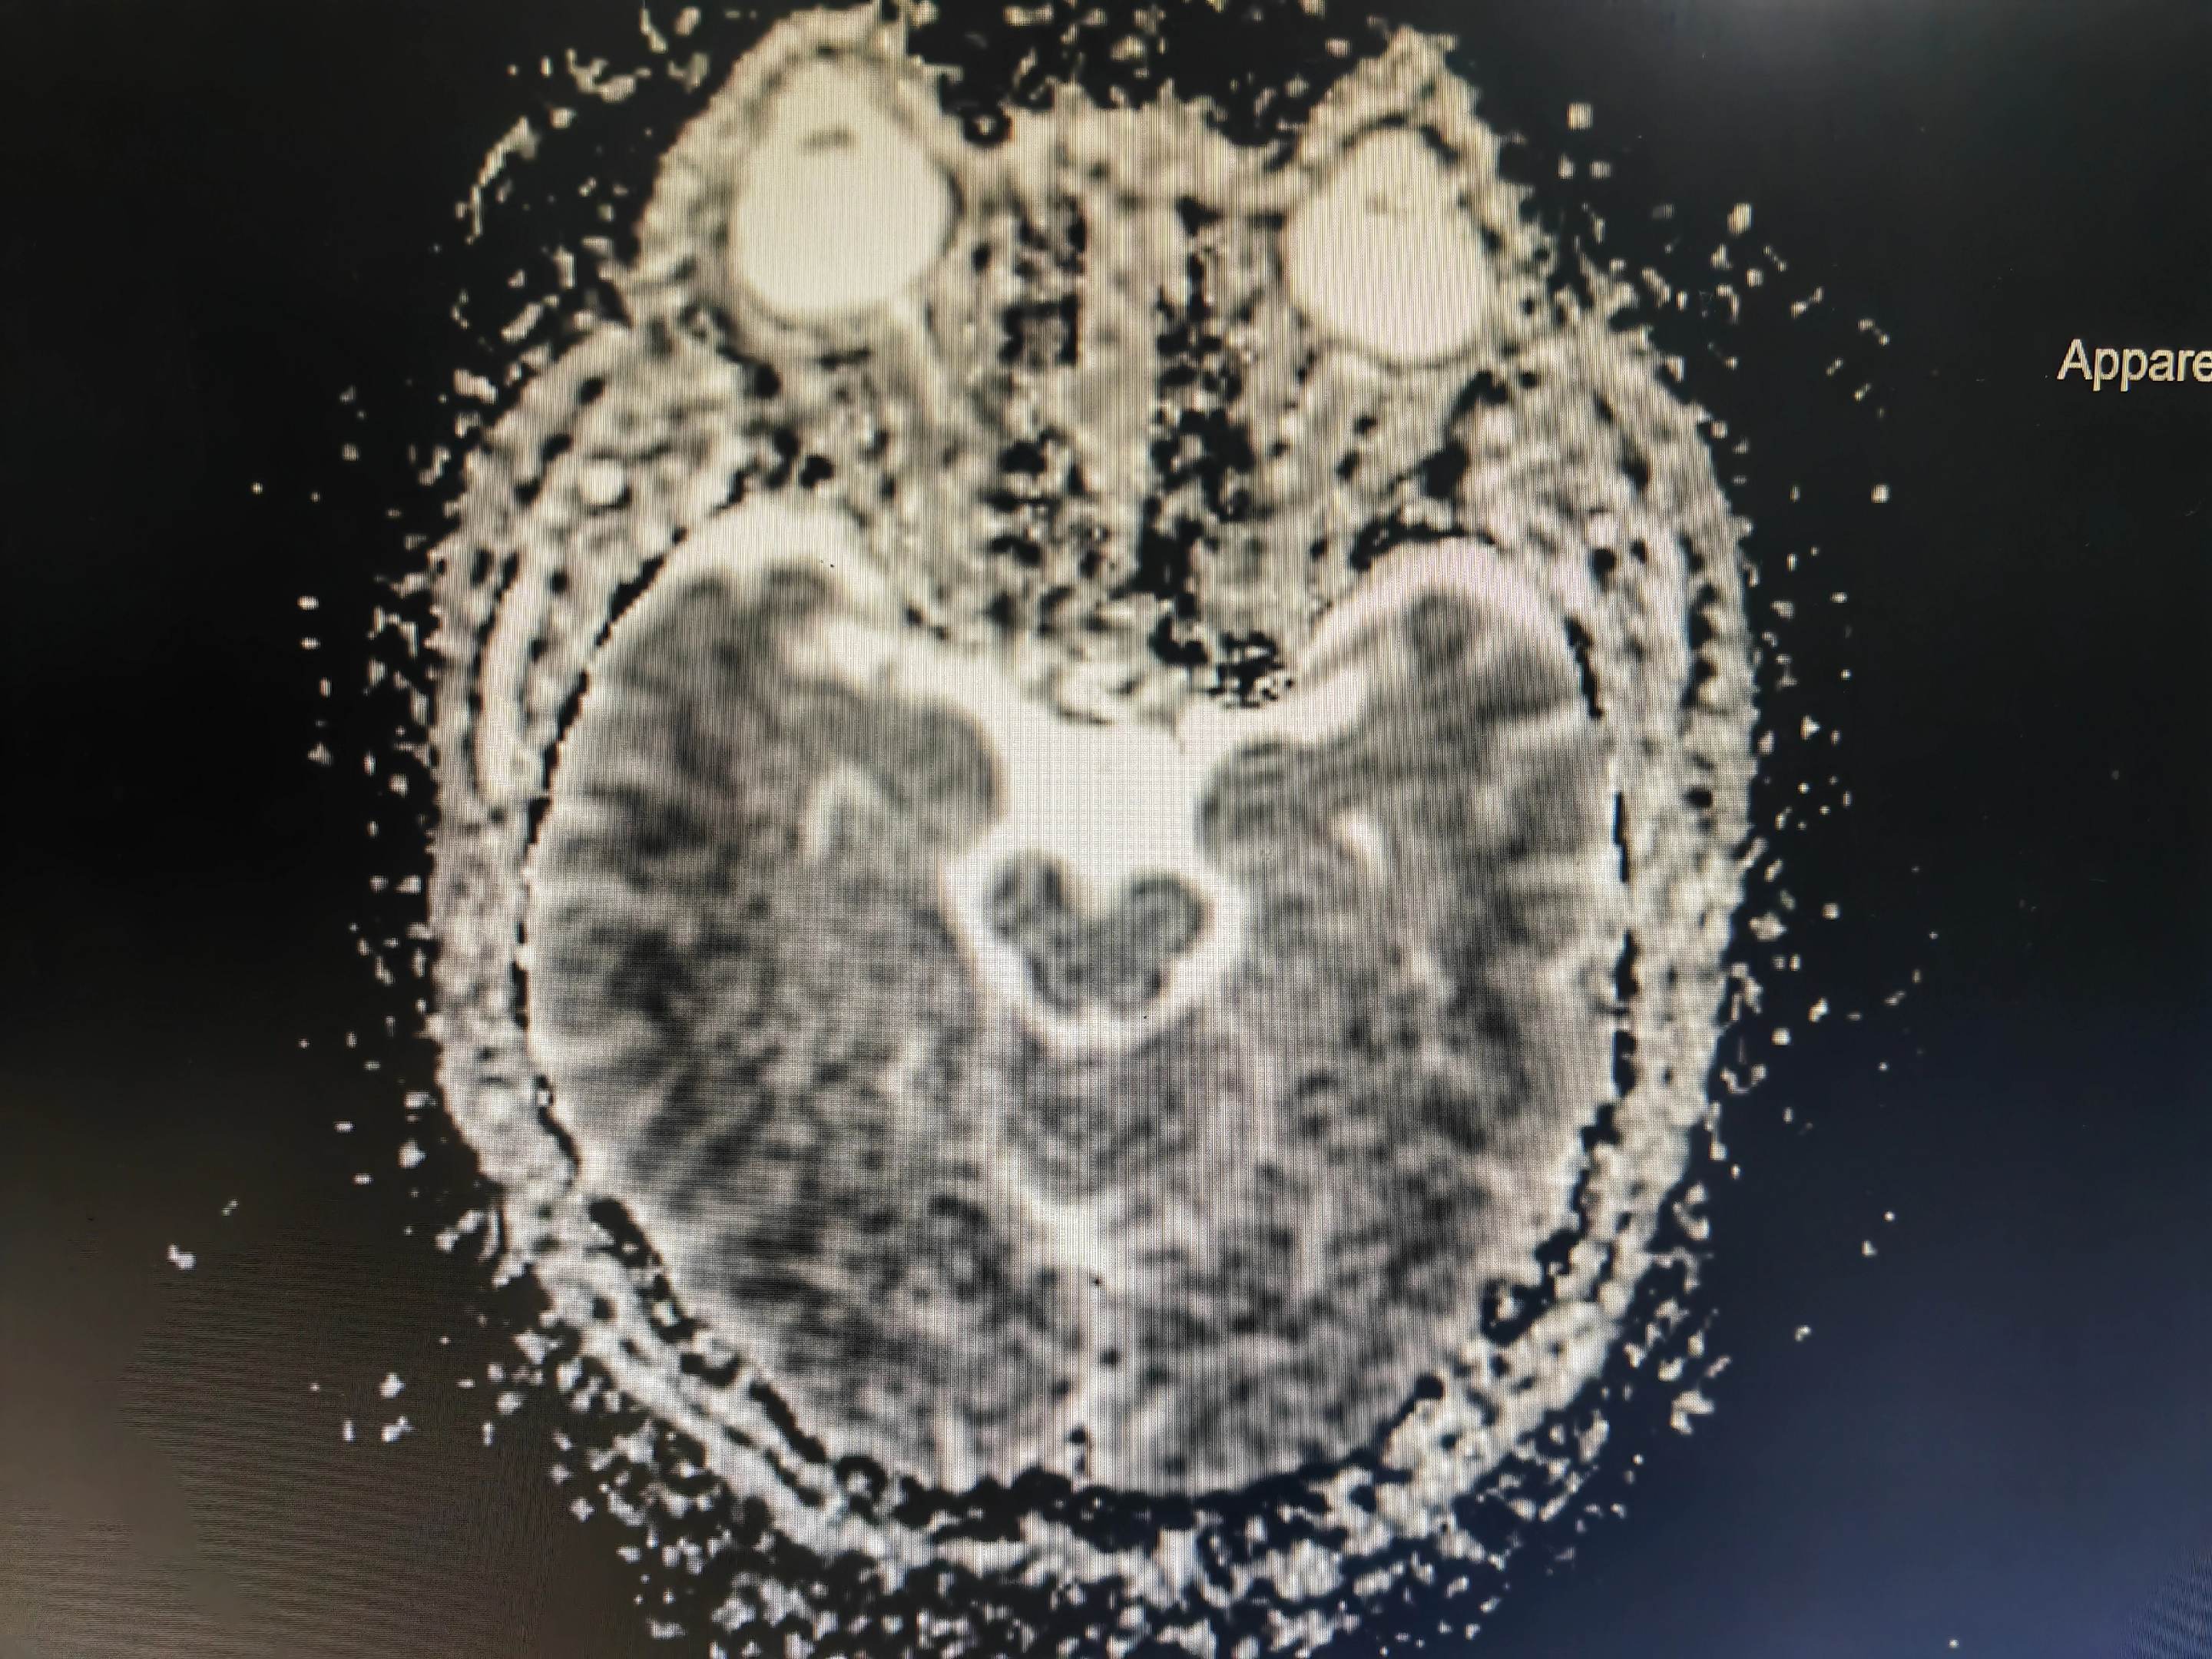

意识模糊伴言语不清的病人 中毒代谢性脑病几种最重要的影像学表现:白色即为受累区域,包括双侧对称性基底节和/或丘脑受累(图A),对称性齿状核受累(图B),皮层灰质受累(图C),对称性脑室周围白质受累(图D),皮质脊髓束受累(图E),胼胝体受累(图F),不对称性白质受累(脱髓鞘疾病;图G),枕顶枕部血管源水肿(图H),脑桥中央受累(I)。